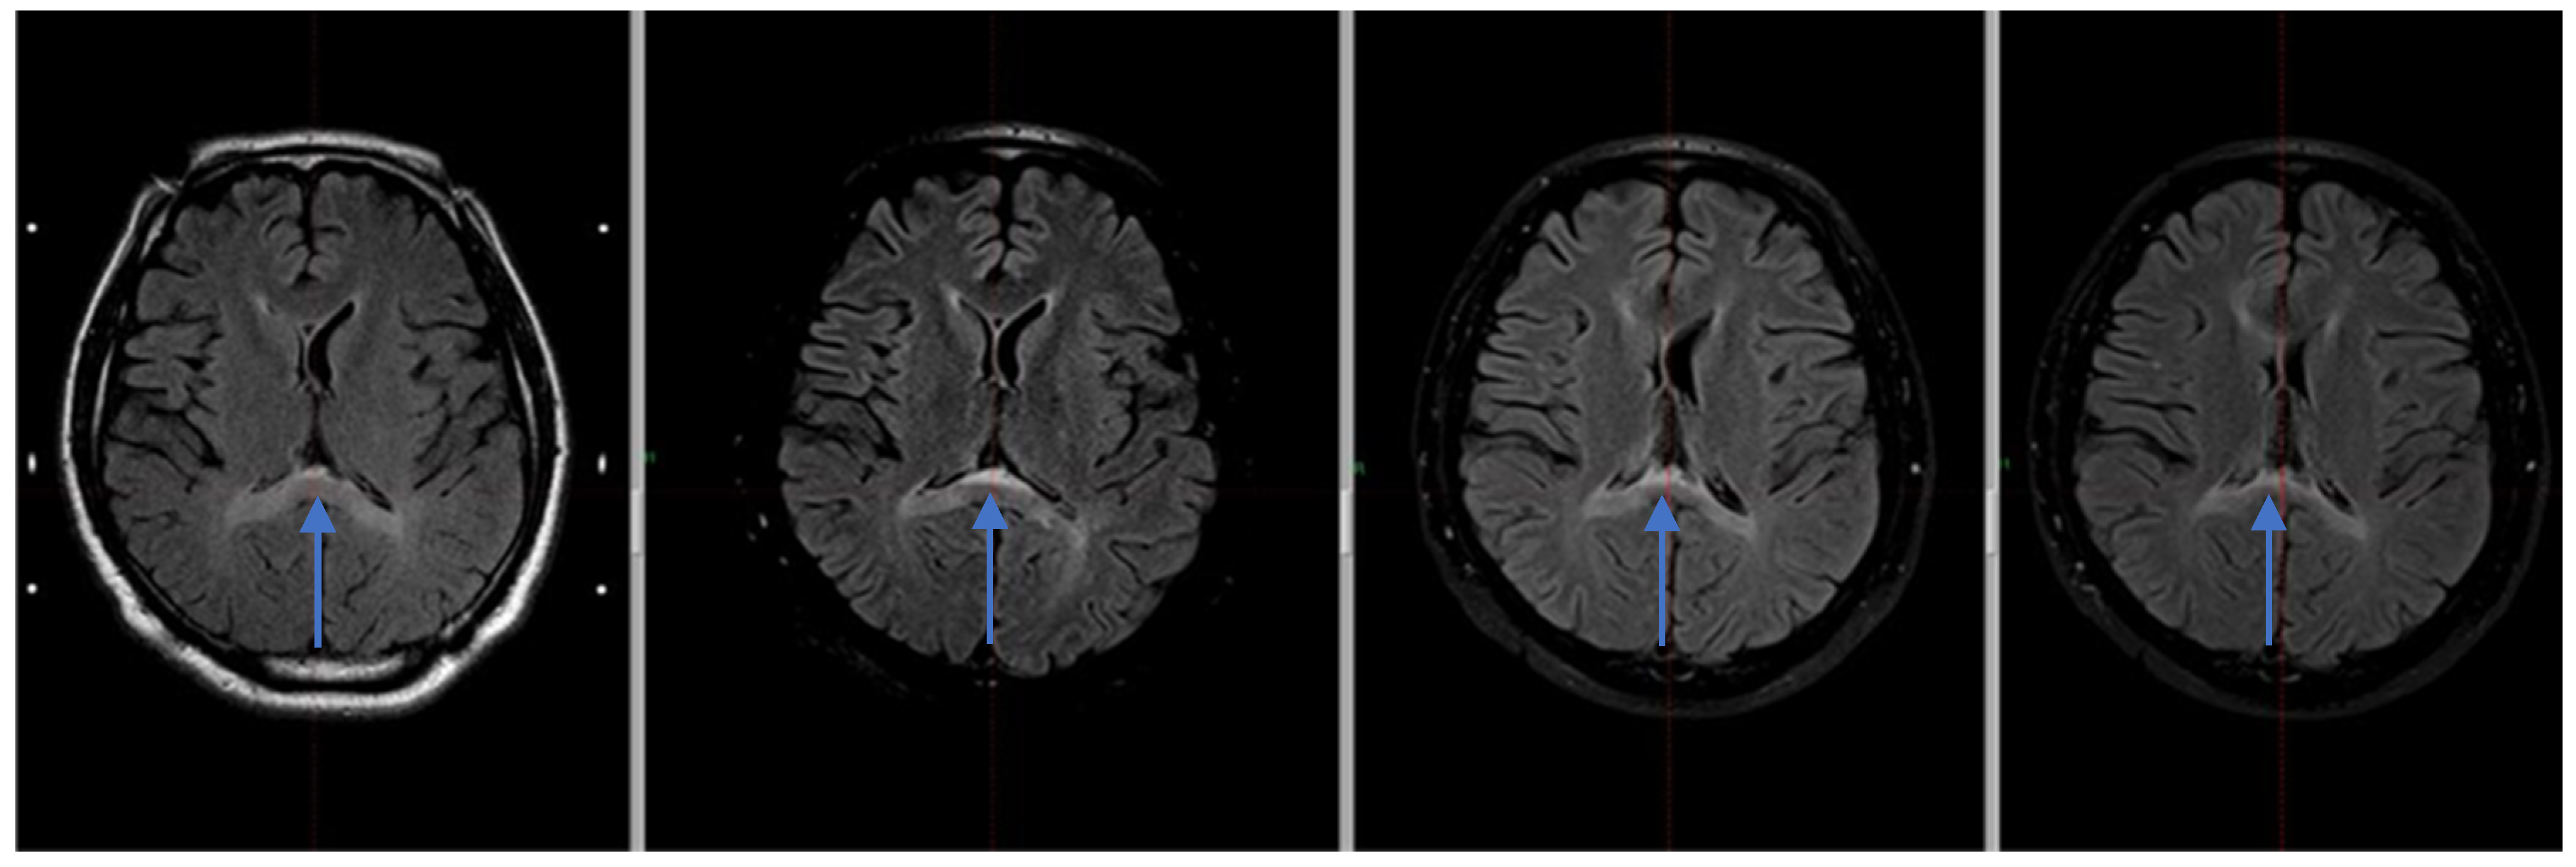

Due to the residual mass of the tumor, the patient was referred for complementary radiotherapy using the Gamma Knife method, which was subsequently performed (Figure 1).

Figure 1. Axial MRI FLAIR images of the cerebellopontine angle following surgical resection of a tumor, demonstrating residual lesion: pre–Gamma Knife radio surgery (2019; top left), one-year post-treatment (top right), and follow-up imaging from 2022 and 2023 (bottom). The treatment target, corresponding to the residual mass, is delineated by the yellow isodose line as planned in the GammaPlan treatment planning system. Yellow circle—the tumor area and its remnants.